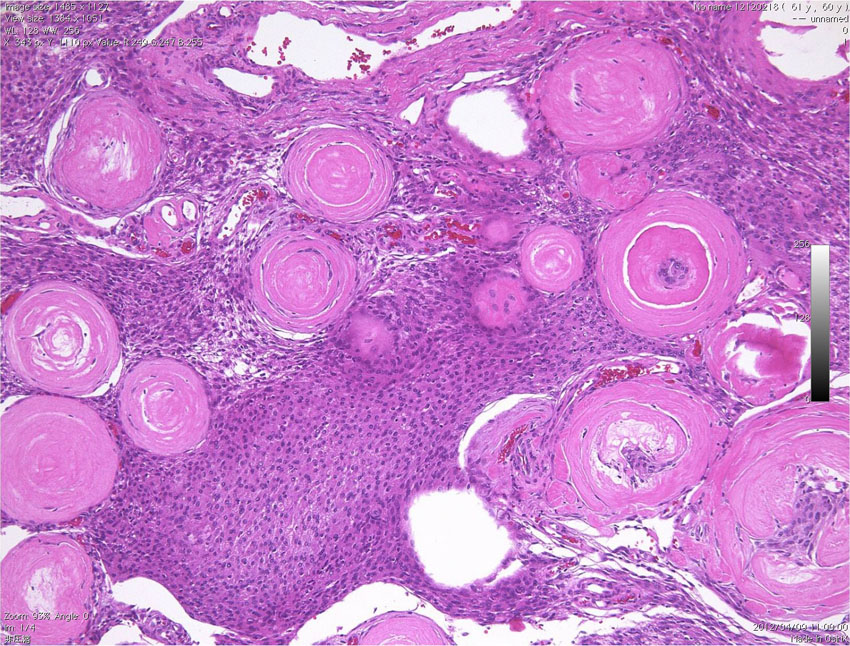

psammomatous meningioma 砂粒腫性髄膜腫

たくさんの砂粒体 psammoma が見られる髄膜腫です。顕微鏡手術では手術中に細かい砂のようなものとして認識されます。この砂粒体は徐々に石灰化 carcification します。写真の中の紫色に変化しているところは,砂粒体が中心部から石灰化して行く過程をみているものです。